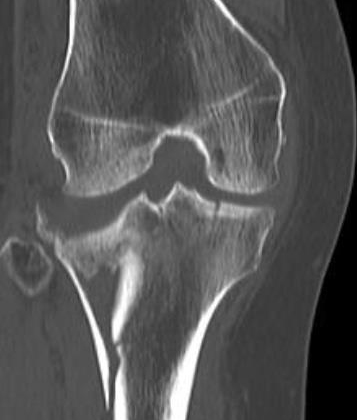

Here is a happy patient after falling off of a stool and fracturing her knee. She had surgery in October and is dancing! You break it! We fix it! Experience life in motion!